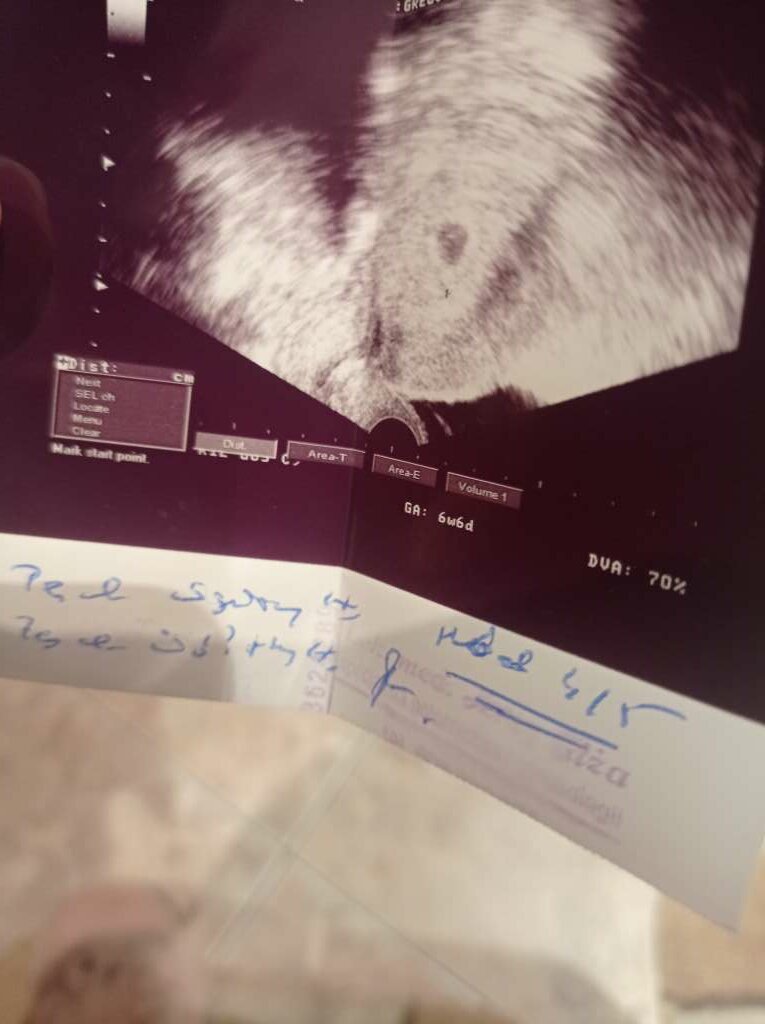

Pecherzyk ciazowy jest, zoltkowy jest cosza 4/5 tydzien wedlug OM 6+6 :( zarodka nie widac

Załączniki

• 6aace2d4-a25f-4ef8-bfea-d10a03bee8c5.jpeg

6aace2d4-a25f-4ef8-bfea-d10a03bee8c5.jpeg

69,3 KB · Wyświetleń: 122